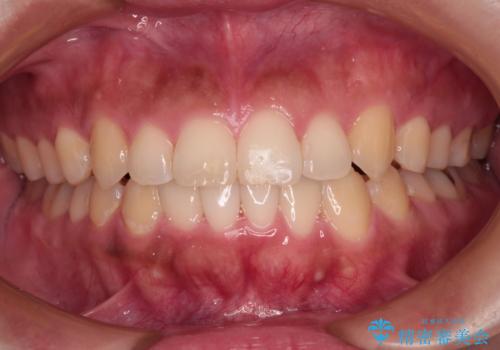

- 前歯のデコボコを気にして来院された患者様です。

叢生と捻転が随所に認められるものの、マウスピースで十分対応可能であったため、インビザラインにて矯正治療を行うこととしました。

マウスピース矯正は毎日しっかりと装着することがとても大切です。

こちらの方はしっかりと指示を守って装着してくださったため、予定通り治療を終えることができました。